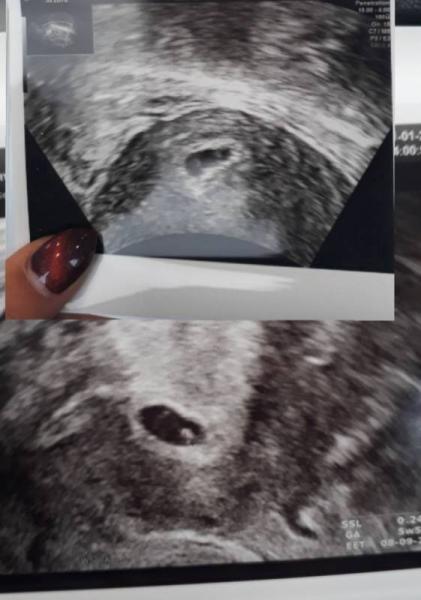

Hallo meine lieben ich bin gerade geschockt. ich war beim Frauenarzt und hab wieder ein Ultraschall Bild bekommen. ich hatte meine letzte Periode am 18. November. rechnerisch wäre ich somit in der 8ten Woche. war am 05 01 beim fa wo ich das erste Bild bekam dieser meinte es sehe nach 5te Woche aus heute war ich bei der Vertretung und dieser sagte mir knallhart die Schwangerschaft wäre nicht mehr aktiv da das Bild nicht zu dem Zeitraum passe. ich lade euch die Bilder hoch das kleinere oben war quasi nach aussehen Woche 5 und das untere eine nicht mehr intakte Schwangerschaft. für mich sieht das Bild aber weiter entwickelt aus wie ein Bild aus der 6ssw. hab den ganzen Tag nur geheult weil ich es nicht begreifen kann da ich eindeutig eine Veränderung sehe.

Es ist eine Entwicklung zu sehen, aber definitiv zu wenig. Es passt nicht zum Schwangerschaftsalter nach letzter Periode, denn demnach wärst du 8. Woche und das Kleine etwa 9mm groß. Vielleicht hat sich aber auch dein ES verschoben. Wie lang war dein Zyklus?

Du schreibst, dass dein Gyn vor 6 Tagen der Meinung war, dass du in der 5 SSW bist. Somit wärst du heute ssw 6 oder 7 und dafür sieht das Bild OK aus. Oder habe ich was missverstanden?

Huhu, ganz ehrlich? Da steht 5+5 auf dem Bild..und das passt..Ich stelle dir meins mal rein von 6+1 ist aber stark vom Arzt rangezoomt..sieht genauso aus wie bei dir! Wird bestimmt alles gut!!! Liebe Grüße, Naddel.

Hallo, also wenn du am 05.01. In der 5. Woche warst, dann wärst du am 11.01. in der 6. Woche gewesen. Und genau das besagt auch das Ultraschall Bildchen. Auf diesem steht unten rechts 5+5, d. h. 6. Schwangerschaftwoche. Trotzdem passt die 5. Ssw nicht zu einem positiven Schwangerschaftstest am 21.12. Leider bleibt dir nichts anderes übrig als noch einmal mindestens (!) eine Woche verstreichen zu lassen und es dann - am besten bei deiner Gyn - nochmal kontrollieren zu lassen. Ich hatte selber mehrere Fehlgeburten und da hatte die Ärztin leider letztendlich immer recht, auch wenn ich mich immer bis zuletzt an einen Strohhalm geklammert habe. Ich habe meine Gyn dabei auch immer als sehr abgeklärt und rational empfunden und das hat mir schwer zu schaffen gemacht. Natürlich ist für die Ärzte eine frühe Fehlgeburt eine Routinesache und medizinisch nicht bedrohlich, aber man selber als betroffene Frau erlebt die Hölle und bekommt den Boden unter den Füßen weggerissen. Rede mit jemandem aus deinem privaten Umfeld, die können dich besser auffangen als so ein doofer Arzt. Sicher hat der Vertretungsarzt gesagt wann du nochmal zur Kontrolle kommen sollst. Ich drücke dir die Daumen... Hannah